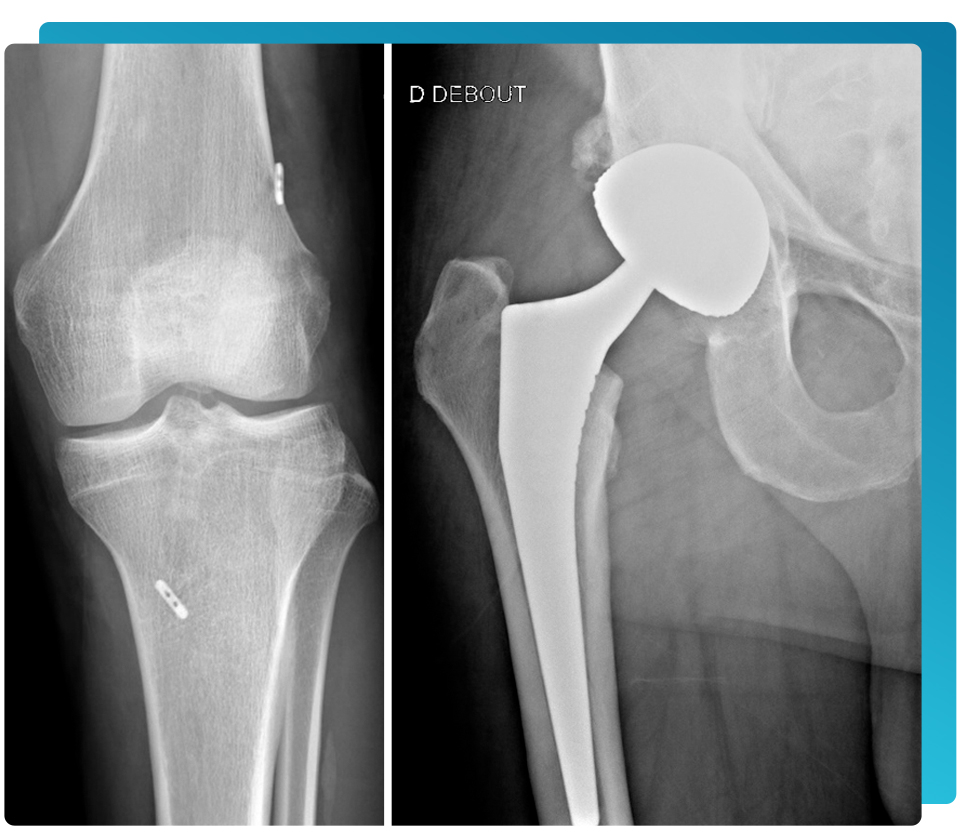

- Prothèse totale ou partielle du genou

- Prothèse totale de hanche par voie postérieure et par voie antérieure mini-invasive